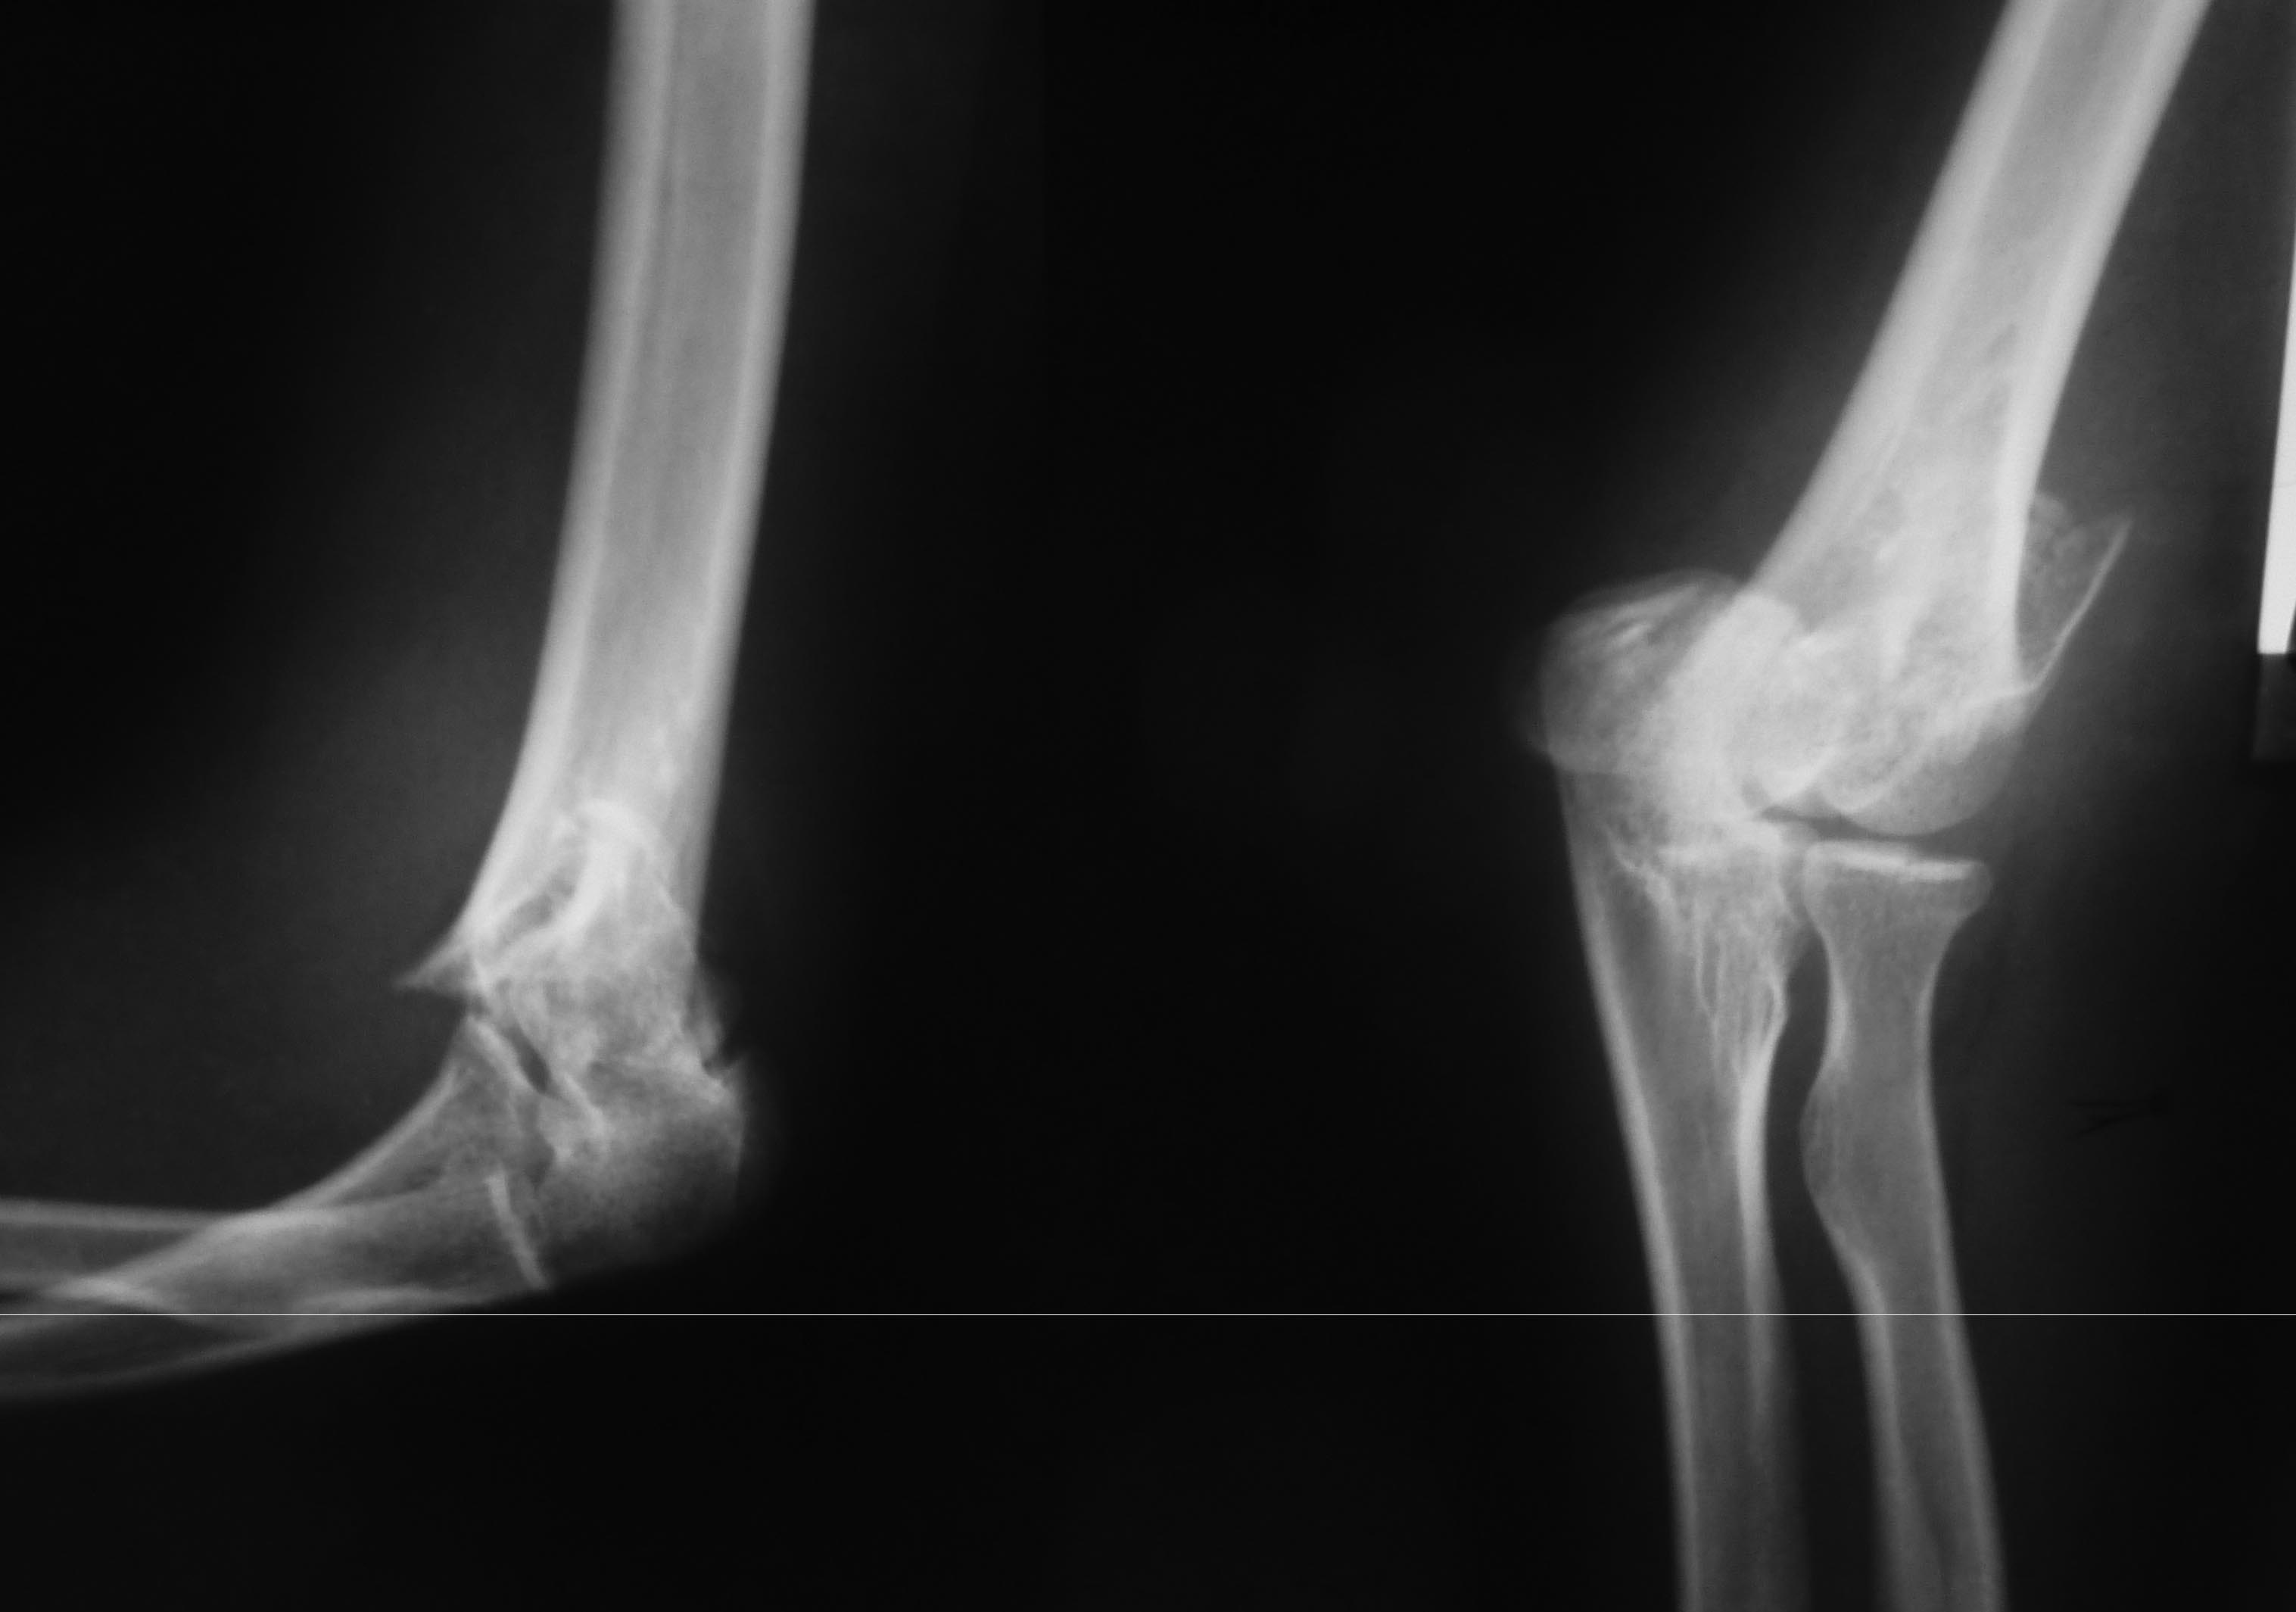

[Ortho] Перелом плечевой и головки лучевой костей (и немного локтевой)

Травма менее суток назад. Пациентке 35 лет. Сосудистых и неврологических

расстройств

конечности нет.

Вопрос: обязателен ли в данном случае остеосинтез головки луча?